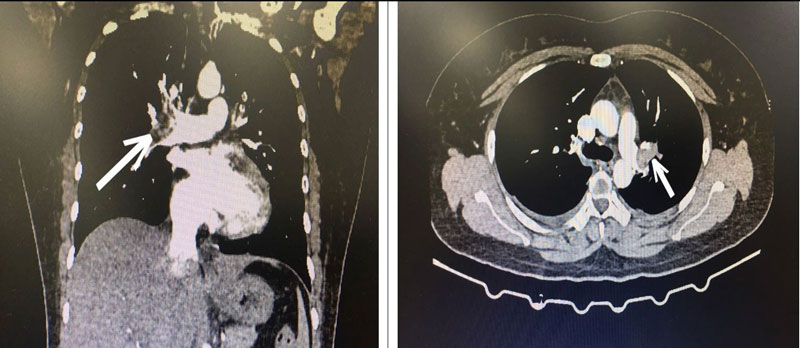

Bác sĩ cấp cứu hướng chẩn đoán tới bệnh thuyên tắc động mạch phổi cấp và quyết định cho chụp CT ngực có tiêm thuốc cản quang. Kết quả là hình ảnh huyết khối động mạch phổi 2 bên.